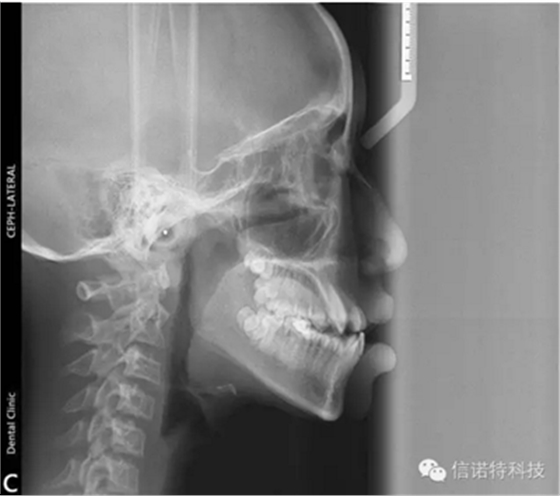

常用X線頭影測量的標(biāo)志點(diǎn)

節(jié)選自《口腔正畸學(xué)》主編:傅民魁 林久祥

蝶鞍點(diǎn)(S.sella):蝶鞍影像的中心。這是常用的一個顱部標(biāo)志點(diǎn),在頭顱側(cè)位片上較容易確定。

鼻根點(diǎn)(N.nasion):鼻額縫的最前點(diǎn)。這是前顱部的標(biāo)志點(diǎn),代表面部與顱部的結(jié)合處。有些X線片上,此點(diǎn)顯示不太清楚,是因?yàn)槠湫螒B(tài)不規(guī)則骨縫形成角度之故。

耳點(diǎn)(P.porion):外耳道之最上點(diǎn)。頭影測量上常以定位儀耳塞影像之最上點(diǎn)為代表,稱為機(jī)械耳點(diǎn)。但也有少數(shù)學(xué)者使用外耳道影像之最上點(diǎn)來代表,則為解剖耳點(diǎn)。

顱底點(diǎn)(Ba.basion):枕骨大孔前緣之中點(diǎn)。一般此點(diǎn)較易確定,常作為后顱底的標(biāo)志。

Bolton點(diǎn):枕骨髁突后切跡的最凹點(diǎn)。

眶點(diǎn)(O.orbitale:)眶下緣之最低點(diǎn)。當(dāng)病人兩側(cè)對稱及在完好的定位下,左右眶點(diǎn)才于同一水平,但實(shí)際上難以達(dá)到。一般X線片上可顯示左右兩個眶點(diǎn)的影像故常選用兩點(diǎn)之間的點(diǎn)作為眶點(diǎn),這樣可減小其誤差。

翼上頜裂點(diǎn)(Ptm.pterygomaxillary fissure):翼上頜裂輪廓之最下點(diǎn)。翼上頜裂之前界為上頜竇后壁,后界為蝶骨翼突板之前緣,此標(biāo)志點(diǎn)提供了確定了上頜骨的后界和磨牙的近遠(yuǎn)中向間隙及位置的標(biāo)志。

前鼻棘(ANS.anterior nasal spine):前鼻棘之尖。前鼻棘點(diǎn)常作為確定腭平面的兩標(biāo)志點(diǎn)之一,但此標(biāo)志點(diǎn)的清晰與否與X線片的投照條件有關(guān)。一般不作近遠(yuǎn)中長度測量所用。

后鼻棘(PNS.posterior nasal spine):硬腭后部骨棘之尖。

上齒槽座點(diǎn)(A.subspinale):前鼻棘與上齒槽緣點(diǎn)間之骨部最凹點(diǎn)。此點(diǎn)僅作為前后向測量所用。

上齒槽緣點(diǎn)(SPr.superior prosthion):上齒槽突之最前下點(diǎn)。此點(diǎn)常在上中切牙之牙釉質(zhì)-牙骨質(zhì)界處。

上中切牙點(diǎn)(UI.upper incisor):上中切牙切緣之最前點(diǎn)。一般上中切牙的測量有兩種方法,一種是以此點(diǎn)與根尖相連作為中上切牙牙長軸來作為角度測量的一個平面,另一種是測量此點(diǎn)與其他結(jié)構(gòu)間的距離。

髁頂點(diǎn)(Co.condylion):髁突的最上點(diǎn)。

關(guān)節(jié)點(diǎn)(Ar.articulare):顱底下緣與下頜髁突頸后緣之交點(diǎn)。關(guān)節(jié)點(diǎn)常在髁頂點(diǎn)不易確定時而代替髁頂點(diǎn)。

下頜角點(diǎn)(Go.gonion):下頜角的后下點(diǎn)??赏ㄟ^下頜支平面和下頜平面交角之分角線與下頜角之相交點(diǎn)來確定。

下齒槽座點(diǎn)(B.supramental):下齒槽突緣點(diǎn)與頦前點(diǎn)間之骨部最凹點(diǎn)。齒槽緣點(diǎn)(Id.infradentale):下齒槽突之最前上點(diǎn)。此點(diǎn)常在下中切牙之牙釉質(zhì)-牙骨質(zhì)界處。

下切牙點(diǎn)(Li.lower incisor):下中切牙切緣之最前點(diǎn)。

頦前點(diǎn)(P.pogonion):頦部之最突點(diǎn)。

頦下點(diǎn)(Me.menton):頦部之最下點(diǎn)。

頦頂點(diǎn)(Gn.gnathion):頦前點(diǎn)與頦下點(diǎn)之中點(diǎn)。

D點(diǎn):下頜體骨性聯(lián)合部之中心點(diǎn)。

這些標(biāo)志點(diǎn)中,有些是在正中矢狀面上,是單個的點(diǎn)。如鼻根點(diǎn)、蝶鞍點(diǎn)等。而有些則是雙側(cè)的點(diǎn),如下頜角點(diǎn),關(guān)節(jié)點(diǎn)等。若由于面部不對稱而使兩側(cè)之點(diǎn)不重疊時,則取二點(diǎn)間的中點(diǎn)作為校正的位置。

額點(diǎn)(G.glbella):額部之最前點(diǎn)。

軟組織鼻根點(diǎn)(NS nasion of soft tissue):軟組織側(cè)面上相應(yīng)的鼻根點(diǎn)。眼點(diǎn)(E.eye):瞼裂之眥點(diǎn)。

鼻下點(diǎn)(Sn.subnasale):鼻小柱與上唇之連接點(diǎn)。

唇緣點(diǎn)(vermilion borders):

上唇緣點(diǎn)(UL′):上唇粘膜與皮膚之連接點(diǎn)。

下唇緣點(diǎn)(LL′):下唇粘膜與皮膚之連接點(diǎn)。

上唇突點(diǎn)(UL):上唇之最突點(diǎn)。

下唇突點(diǎn)(LL):下唇之最突點(diǎn)。

軟組織之頦前點(diǎn)(Pos.pogonion of soft tissue):軟組織頦之最前點(diǎn)。

軟組織頦下點(diǎn)(Mes.menton of soft tissue):軟組織頦之最下點(diǎn)。

咽點(diǎn)(K):軟組織頸部與咽部之連接點(diǎn)。